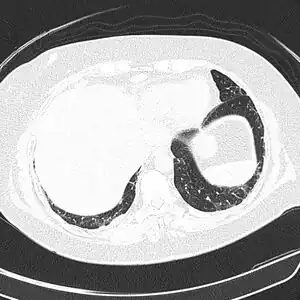

![]() ![]() text: From left to right: Cryptococcosis lung, cryptococcosis brain | |

CT scan lungs: mass in right upper lobe